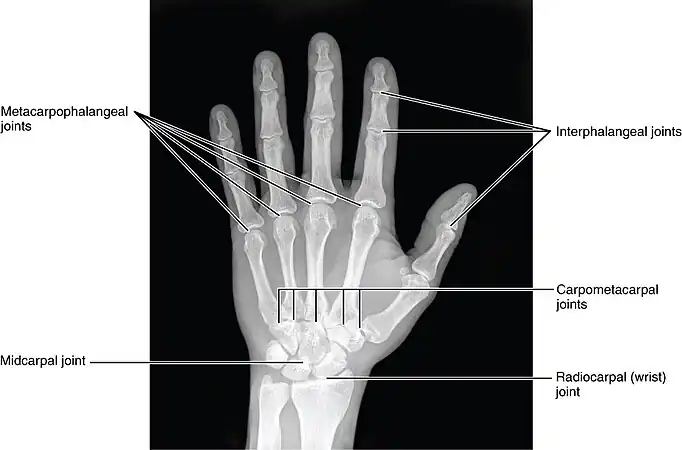

Joints of the hand, X-ray

The interphalangeal joints of the hand are the hinge joints between the phalanges of the fingers that provide flexion towards the palm of the hand.

There are two sets in each finger (except in the thumb, which has only one joint):

• "proximal interphalangeal joints" (PIJ or PIP), those between the first (also called proximal) and second (intermediate) phalanges

• "distal interphalangeal joints" (DIJ or DIP), those between the second (intermediate) and third (distal) phalanges